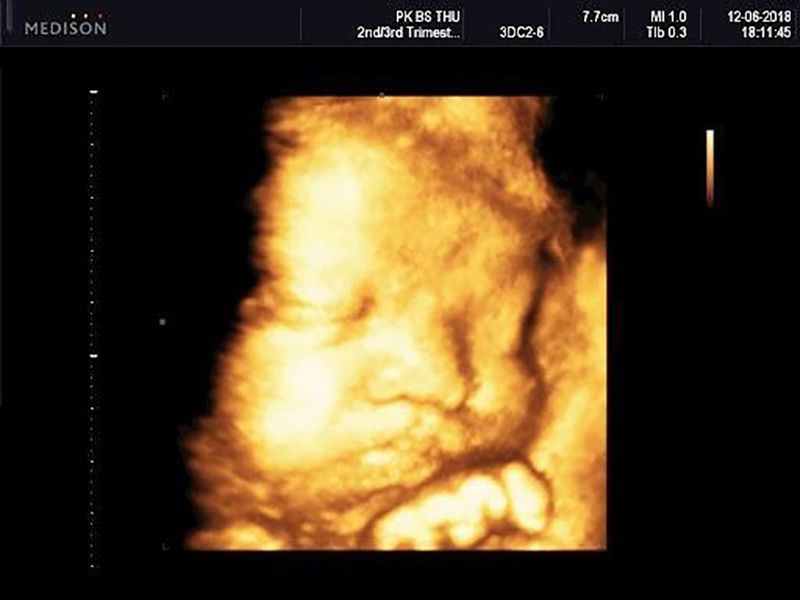

Siêu âm 4D là kỹ thuật siêu âm 4 chiều với một chiều thời gian và 3 chiều không gian, nhờ vậy bác sĩ và mẹ có thể nhìn rõ được cử chỉ, hình hài đáng yêu của bé trong thời gian thực hiện. Thậm chí nếu may mắn, bạn còn có thể chớp được hình ảnh thiên thần nhỏ đang cười, khóc nhè hay cau mày,…

Có thể nói, siêu âm 4D đã đưa vào công nghệ chẩn đoán hình ảnh một bước ngoặt hiện đại mới, cải tiến hơn so với siêu âm 2D và 3D. Khác với kỹ thuật 2D cho ra hình ảnh đen trắng với những con số chưa rõ ràng thì siêu âm 4D sẽ cho hình ảnh màu, sắc nét, chính xác, chân thật và tạo ra những hiệu ứng giống như đang xem video trực tiếp. Qua đó, bác sĩ sẽ dễ dàng phát hiện được những dị tật bẩm sinh ở trẻ như hở hàm ếch, các dị tật về não, hội chứng Down, thai phù,… để có hướng can thiệp sớm.

Siêu âm 4d

Kỹ thuật siêu âm 4D được rất nhiều chị em yêu thích